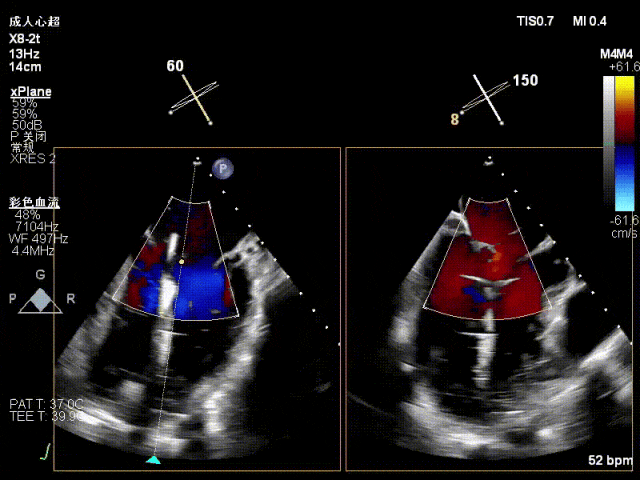

术中超声要点

术前术后对比图

术前

术后

术后,出院检查报告显示夹子位置固定,二尖瓣、三尖瓣及主动脉轻微反流,左房增大,左室内径正常上限,EF值正常下限(WMSI 1分)。